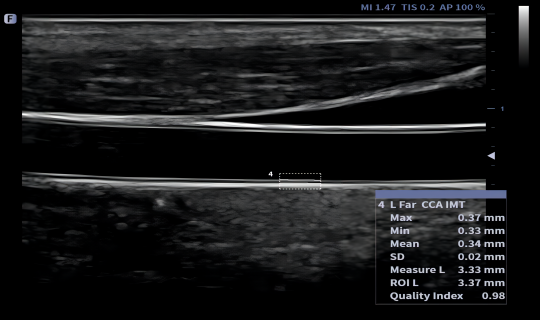

Auto IMT

fAssist